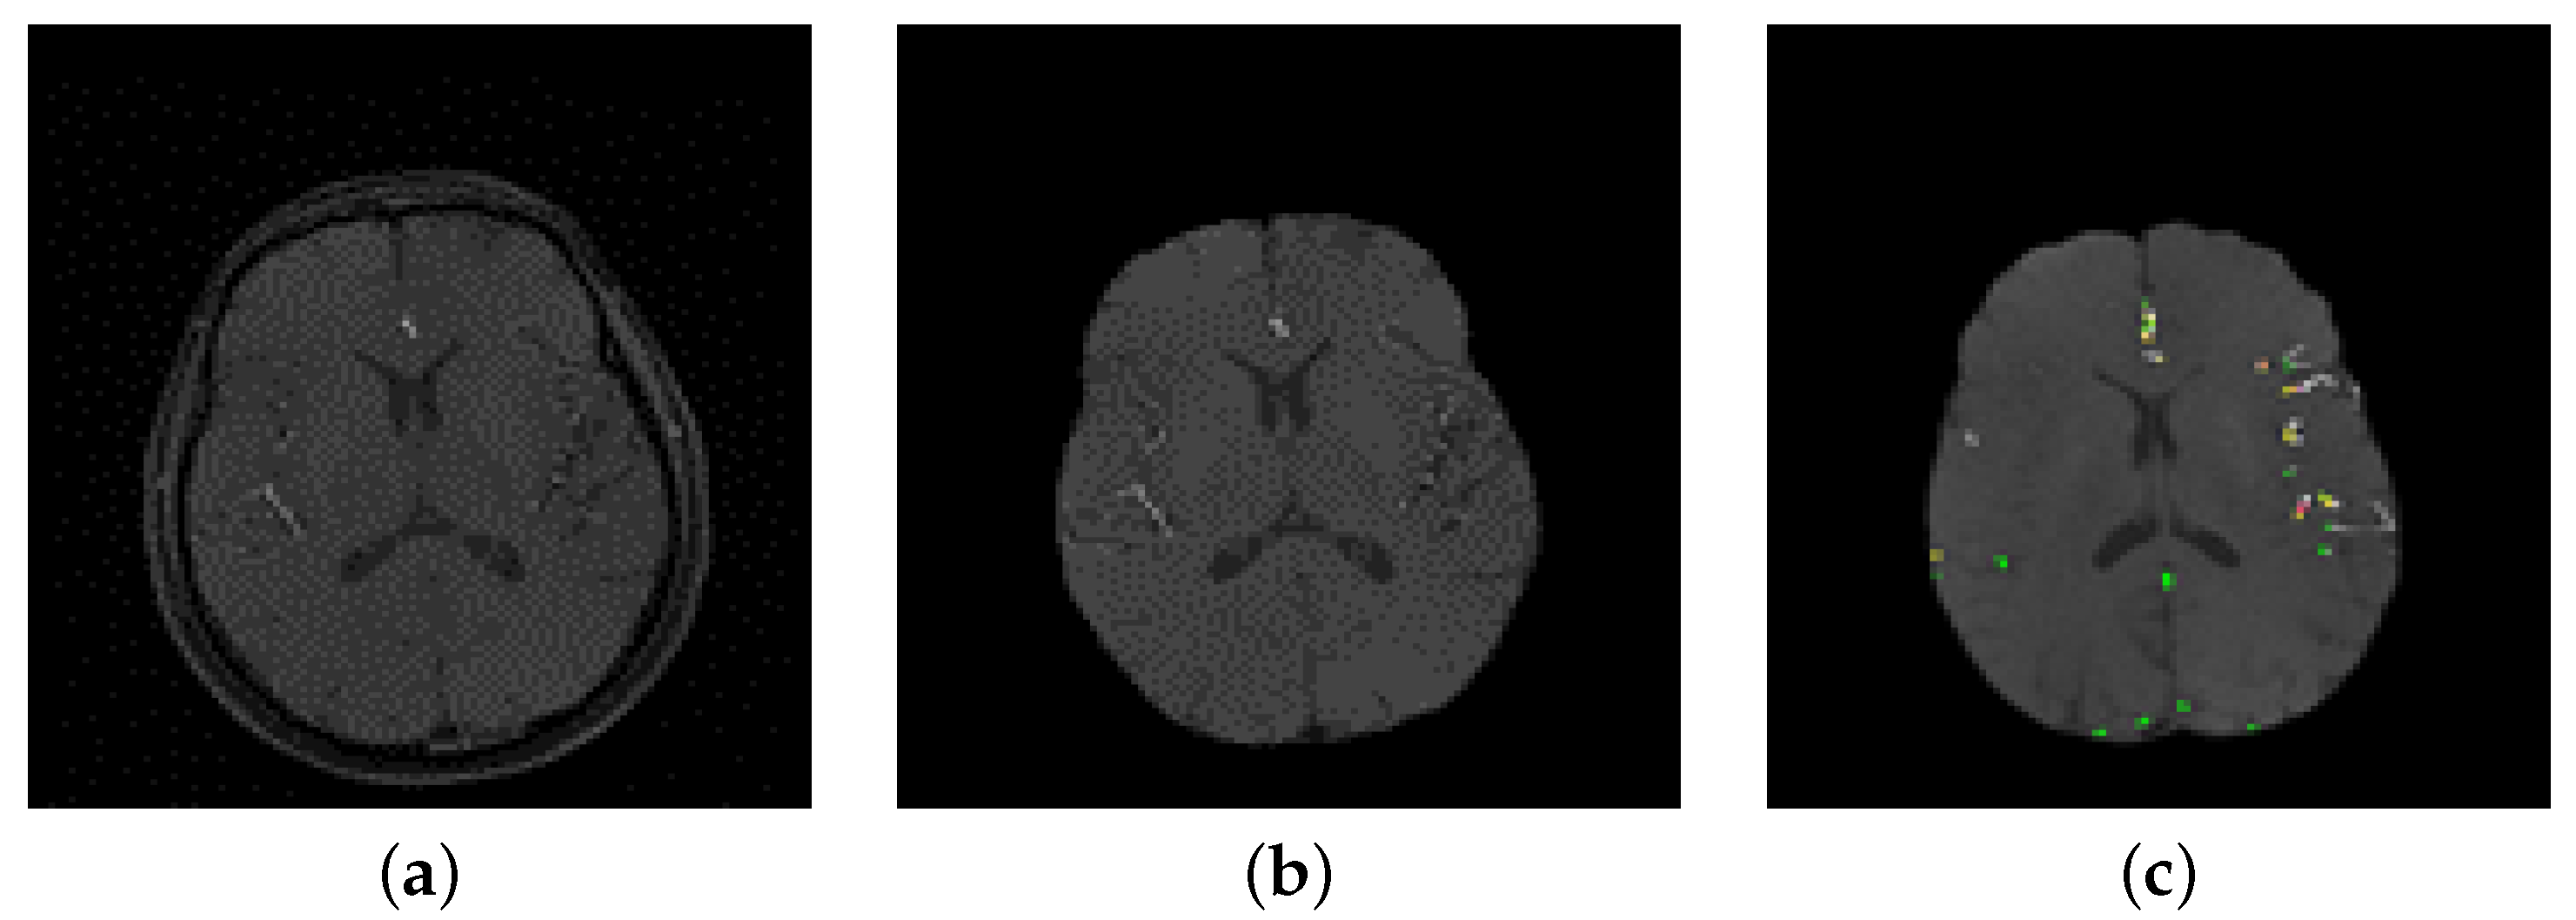

2.1. Cerebral Vasculature Segmentation